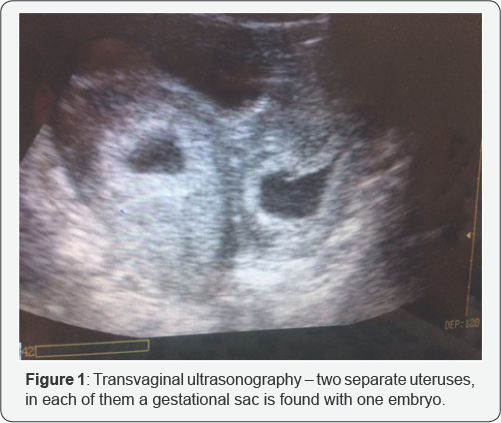

It is about a 20 year old patient, who is sent to the clinic for termination of the found undeveloping multiple pregnancy. The ambulatory gynecology examination showed two separate uteruses, and in each of them was visualised a gestational sac with one embryo, fitting 7-8 gestational week and lack of heart pulsations. The patient's symptomes were weak genital bleeding, with no pain syndrome. That fit the clinical presentation of a missed abortion. Our gynecology examination showed the presence of a longitudinal septum of the vagina around 3 cm and to the left and right of it-two separate uterine cervixes. Transvaginal ultrasonography visualised two gestational sacs with two embryos, without heart activity, localized in two separate uterine cavities (Figure 1). The two uteruses were fitting for the amenorrhea duration - 7-8th gestational week. We diagnosed uterus didephys with missed abortion of two embryos in two separate gestational sacs, each of them localized in a separate uterine cavity.